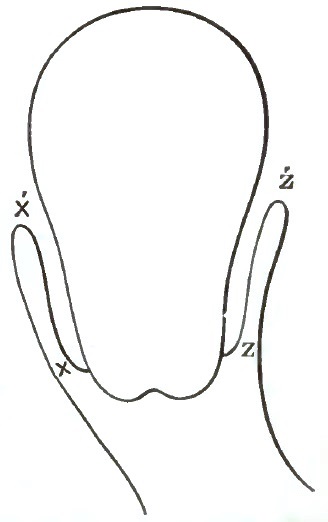

| 7. | THE EMMET CURVES (PESSARY) |

| 8. | THE ALBERT SMITH CURVES (PESSARY) |